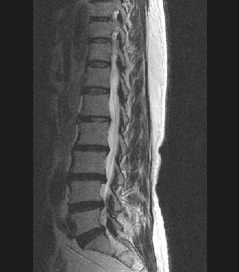

• 척추 방사선 사진2